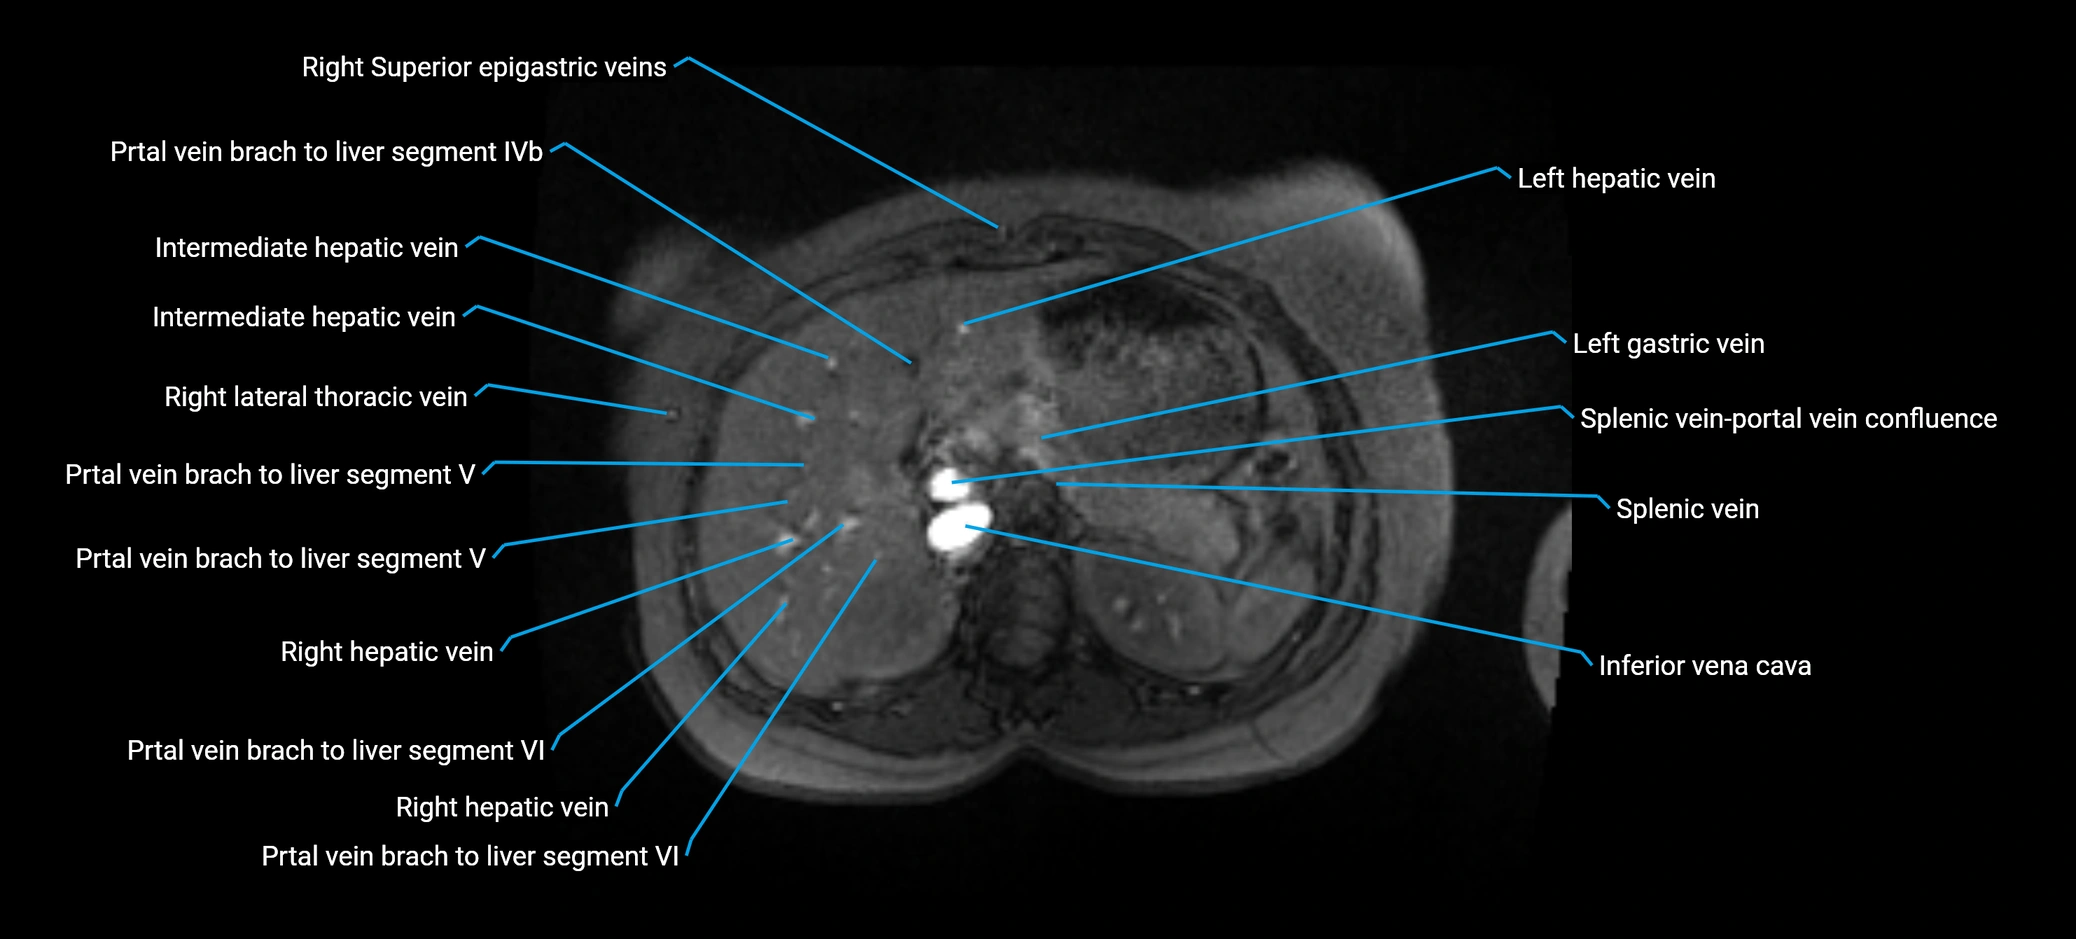

MRI image

image